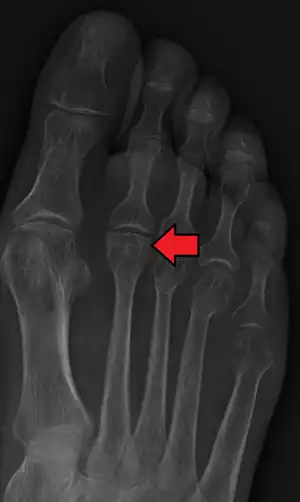

Freiberg disease as seen on plain film

Freiberg disease, also known as a Freiberg infraction, is a form of avascular necrosis in the metatarsal bone of the foot. It generally develops in the second metatarsal, but can occur in any metatarsal. Physical stress causes multiple tiny fractures where the middle of the metatarsal meets the growth plate. These fractures impair blood flow to the end of the metatarsal resulting in the death of bone cells (osteonecrosis). It is an uncommon condition, occurring most often in young women, athletes, and those with abnormally long metatarsals. Approximately 80% of those diagnosed are women. [1]